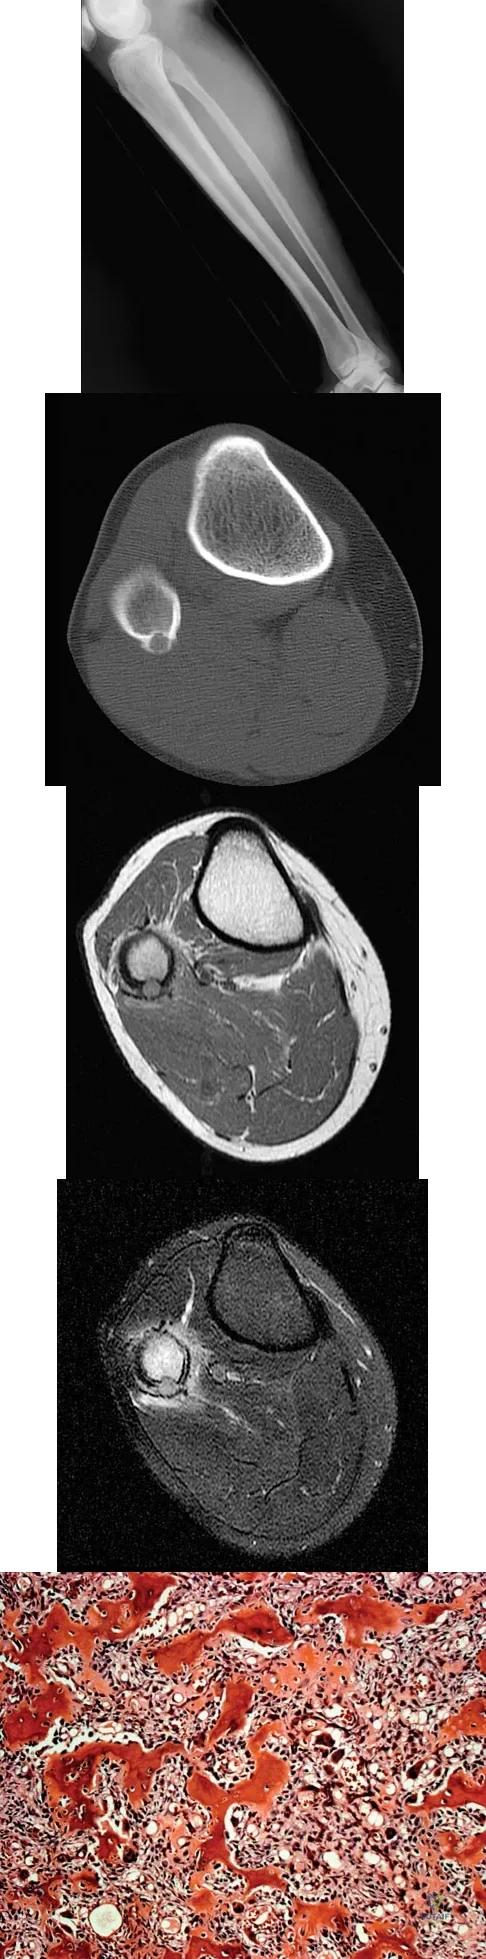

A 23-year-old man has had right posterolateral knee pain and occasional lateral calf dysesthesias for the past 8 months. A radiograph, CT scan, MRI scans, and a biopsy specimen are shown in Figures 62a through 62e. What is the most likely diagnosis?